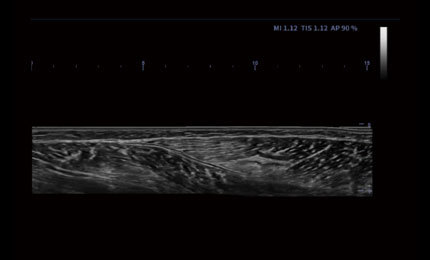

Rozszerzone pole widzenia wyświetla więcej informacji obrazowych bez utraty jakości obrazu. Jest wygodnym podejściem do dużych organów, zwłaszcza struktur układu mięśniowo-szkieletowego. Posiada wskazania dotyczące kierunku i prędkości skanowania.